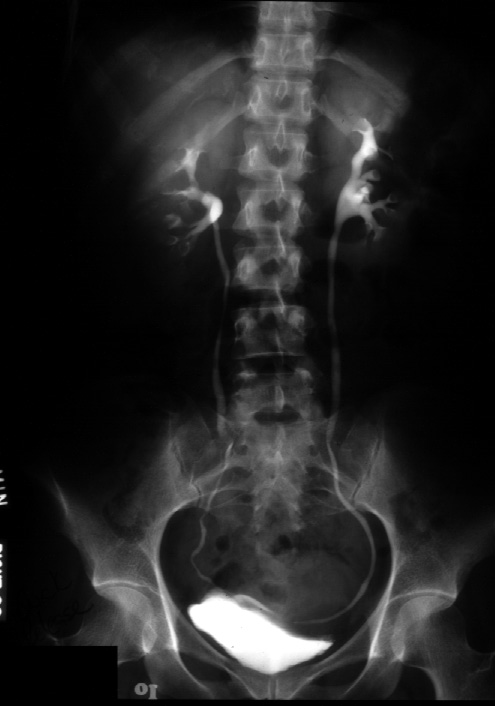

Note.  This is a 10 minute film from an excretory urogram.

Identify -- renal contour, the calyces, the renal pelvis, the ureter, and the bladder